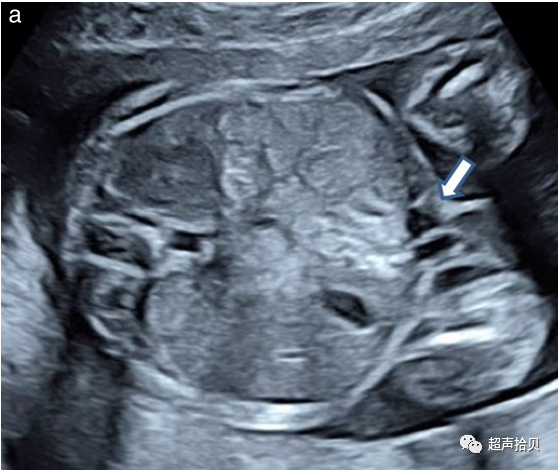

应常规评估胎儿颅骨的四个方面:大小、形态、完整性和骨密度。可在胎头部测量或评估大脑结构完整性的同时观察上述特征(图 2)

1. 大小:测量方法见前文生物测量部。

2. 形态:颅骨通常呈椭圆形,无局部突起或缺损,仅在颅缝处有细窄的回声失落。形态异常(如柠檬头、草莓头、三叶草形头)应记录并予以进一步检查。

3. 完整性:无颅骨缺损。极少数情况下,偶见脑组织通过额部、枕部的缺陷向外膨出,其它部位的脑膨出也可发生。

4. 骨密度:正常的颅骨密度表现为连续高回声结构,仅在特定解剖位置颅缝处有中断。若颅脑结构消失或胎儿大脑结构过渡清晰显示时,应怀疑颅骨钙化不良(例如成骨不全,低磷酸盐血症);

图2胎儿头部的横切面,显示标准的经脑室(a)、经小脑(b)和经丘脑(c)扫描平面。经脑室和经丘脑平面允许评估大脑半球区域的解剖完整性。经小脑平面允许评估后颅窝的小脑和大池(CM)。CP-脉络膜丛、CSP-透明隔腔、TH-丘脑。